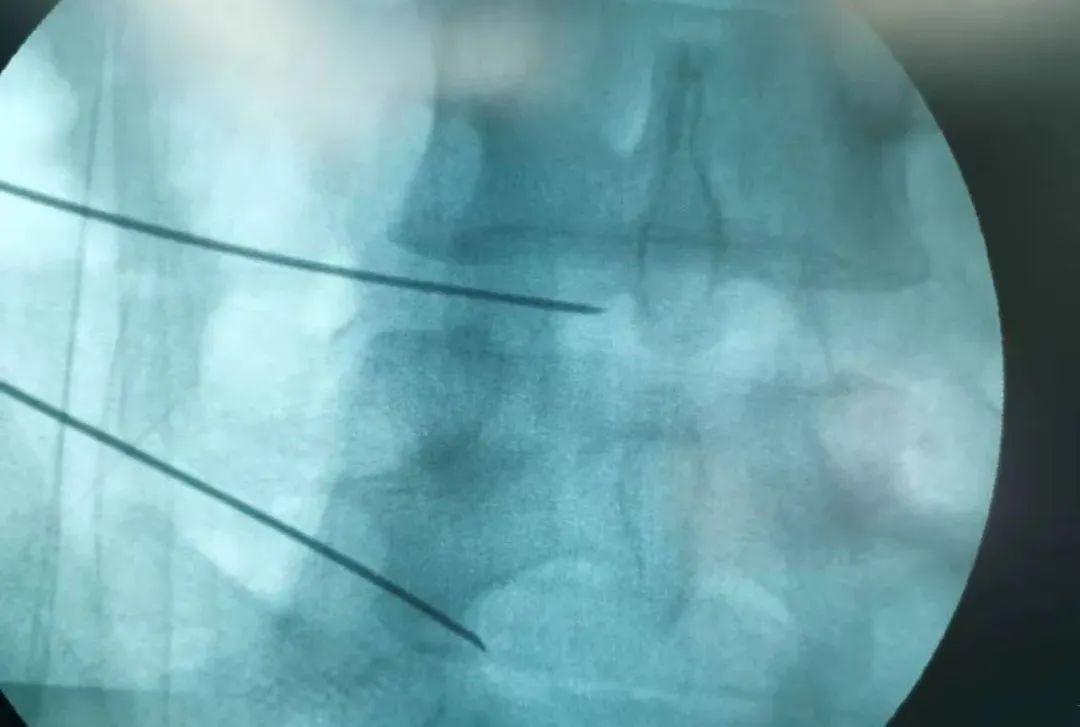

2022年3月15日上午,赵学刚主任为其成功实施了经皮穿刺腰椎间盘射频消融术,手术顺利,术后症状消失,患者自行走回病区。

经皮穿刺腰椎间盘射频消融术

是一种腰椎微创脊柱介入方法

通过专用射频针经过腰椎皮肤

主要从侧方进入椎间盘

进入椎间盘方法

一般需要在C臂机监视下

准确达到椎间盘突出的靶点部位

即突出部位

通过专用射频针

直达突出部位